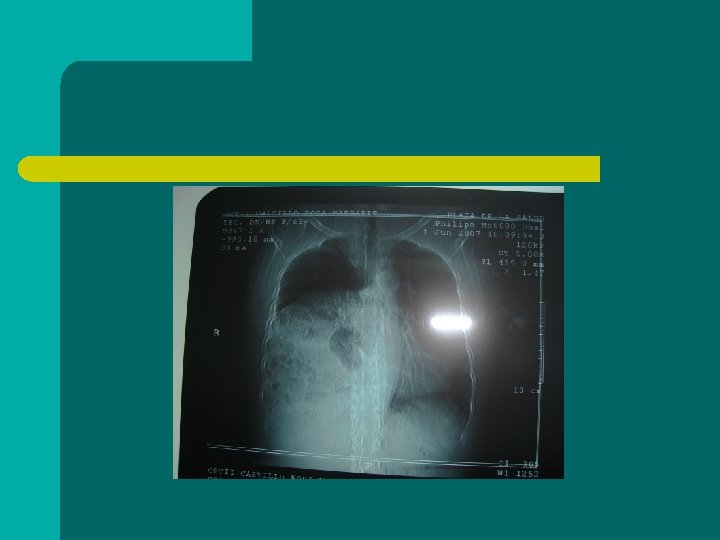

Hernias diafragmaticas l Debilidades naturales: bockdalet y morgani. l Congenitas l Adquiridas: por trauma abierto o cerrado Mas fc lado izq. Lado der. peor pronostico l

sintomatologia l Trastornos respiratorios. l Trastornos abdominales ( ABDOMEN AGUDO)

DIAGNOSTICO l l Historia clinica Gabinete ( Rx, levin, tomografia )

Diagnostico